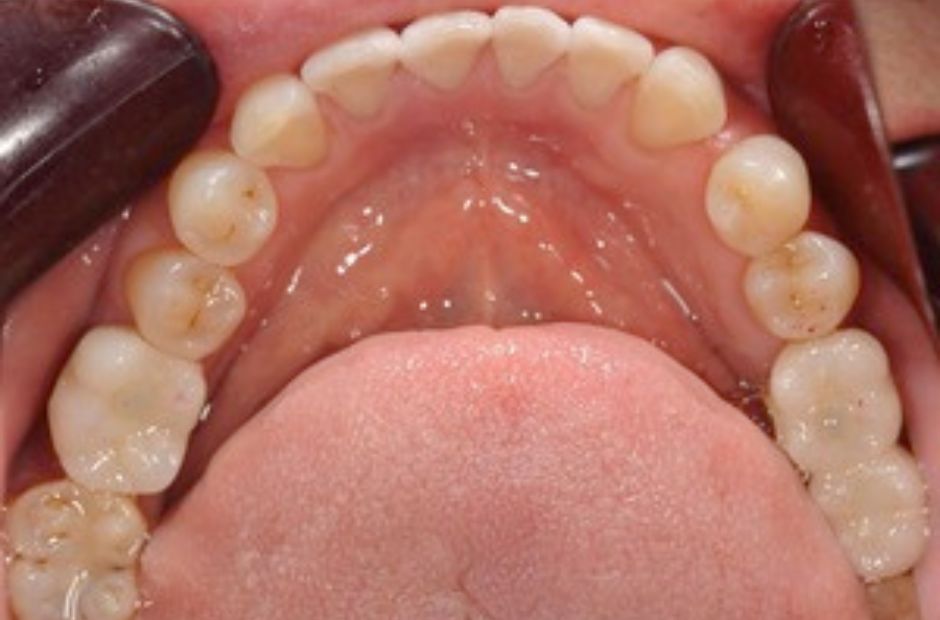

case.03

自然な歯の保存に成功

インプラント治療を希望されていた中高年の患者様が来院されましたが、詳細な検査の結果、虫歯が進行していないことが判明しました。このため、インプラントではなく、根管治療を選択し、自然な歯を保存することに成功しました。この治療は、自然な歯の重要性を重視し、患者様の口腔健康を最優先に考える当院のアプローチを反映しています。治療後、患者様は自然な歯を保つことができ、日常生活の質の向上を実感されました。